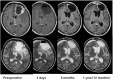

Figures